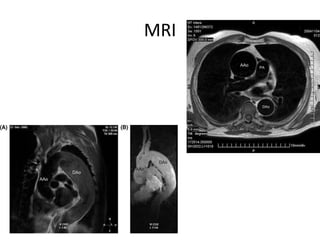

MRI

MRI •Desventajas : Mayor tiempo Metales Pcte inestable